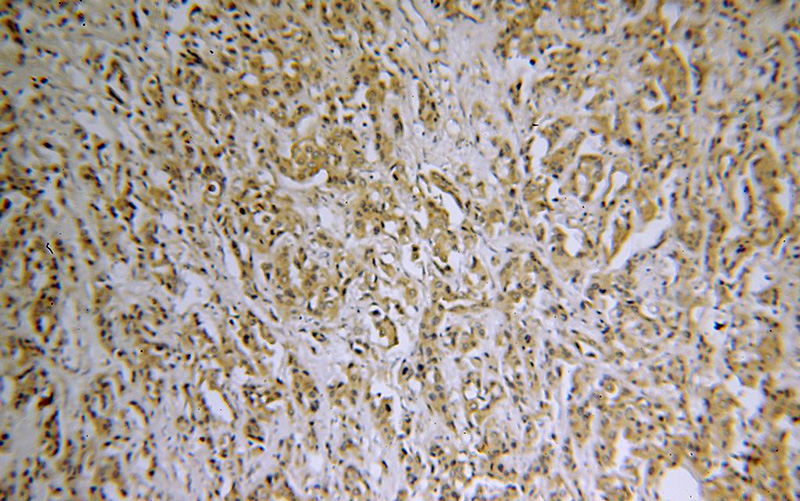

SH3PXD2A Rabbit Polyclonal antibody. Positive IHC detected in human breast cancer tissue. Positive IF detected in HepG2 cells. Positive WB detected in HeLa cells, HepG2 cells. Observed molecular weight by Western-blot: 140-150 kDa

Immunohistochemical of paraffin-embedded human breast cancer using Catalog No:115262(SH3PXD2A antibody) at dilution of 1:50 (under 10x lens)

SH3PXD2A is also named as FISH, KIAA0418, SH3MD1, TKS5. SH3PXD2A contains an amino-terminal PX domain followed by five SH3 domains. It is a cytoplasmic protein in normal fibroblasts(PMID:19464300).The p140 and p130 forms of SH3PXD2A may be generated by other splice variations. The complexity of SH3PXD2A isoforms is also evident in different cell types. For example in human platelets a single band of 150kDa was detected, whereas all three forms were found in human fibroblasts and vascular smooth muscle cells(PMID:9687503).This antibody is specific to SH3PXD2A.